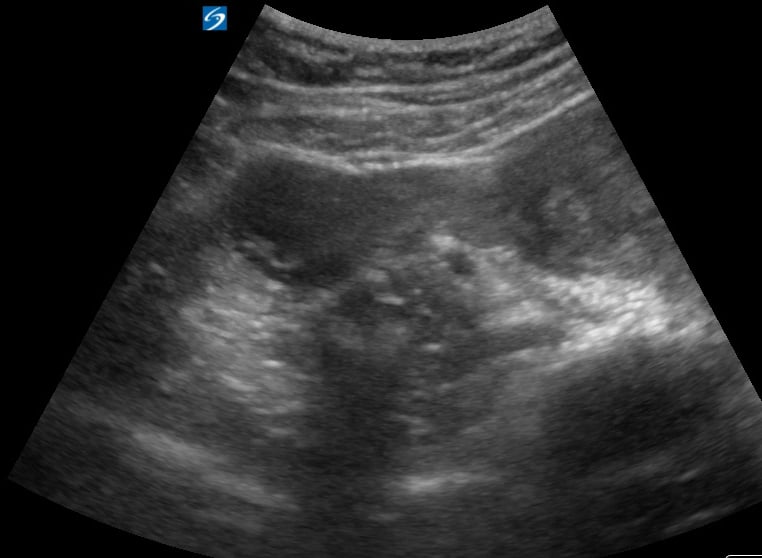

An ovarian cyst is a fluid-filled sac that develops on or within an ovary. Common in OBGYN, most ovarian cysts are benign and resolve spontaneously, but some may cause symptoms like pelvic pain or pressure, or indicate underlying conditions like polycystic ovary syndrome (PCOS). Ultrasound is the primary imaging modality for detecting and characterizing these cysts, providing crucial details on their size, shape, and internal features.

Accurate ultrasound assessment is vital for differentiating simple cysts from more complex or suspicious masses, guiding appropriate medical management and follow-up in gynecological practice. Early detection and precise characterization through medical ultrasound enhance diagnostic accuracy and optimize patient care.